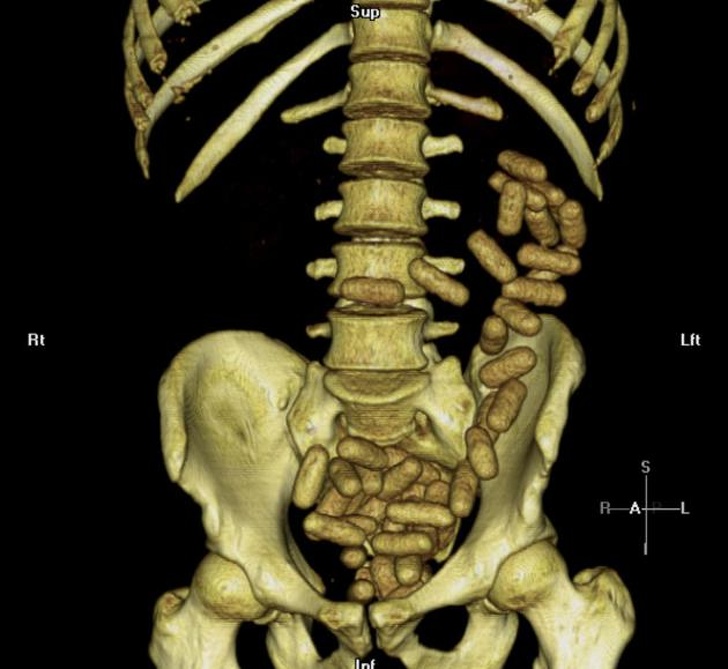

9. КТ черевної порожнини кур'єра, який попався на перевезенні заборонених речовин